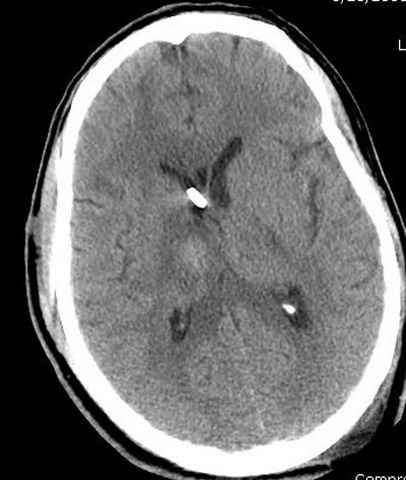

Наблюдается службой травмы и нейрохирургии (ICP) Increased Intracranial Pressure by ventricular cateter

больной без сознания, со слов нейрохирурга, наблюдается положительная динамика в нейрохирургическом статусе.

монииторинг

-Согласен, рана до прихода пластического хирурга была 38х13 см, можно было постараться закрыть сверху, а в нижнем отделе где был ожог, применить кожную пластику меньшим размером. К моему удивлению и разочарованию, когда вернулся из другой операционной (шли пареллельные операции), он уже успешно заканчивал свое дело. Кстати недавно разговаривал с нейрохирургом, он снял ICP (intracranial prеssure monitor), внутричерепное давление стабилизировалось, ортопеды и хирурги закончили с лечением, теперь длительное неврологическое восстановление.